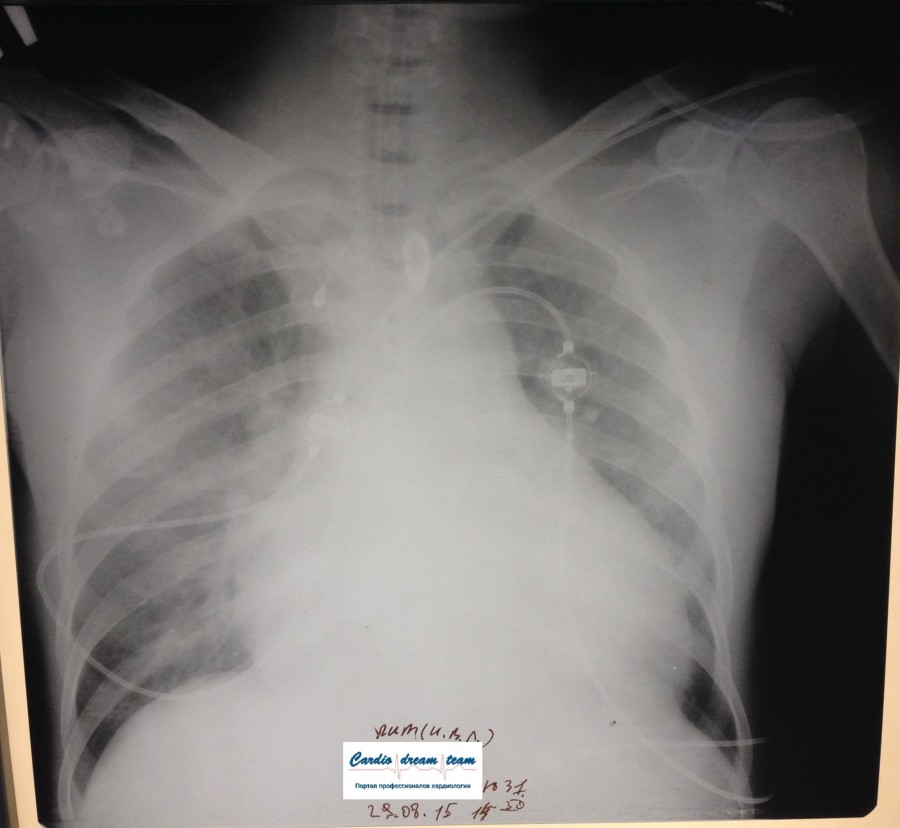

Пневмония

полисегментарная пневмония слева.